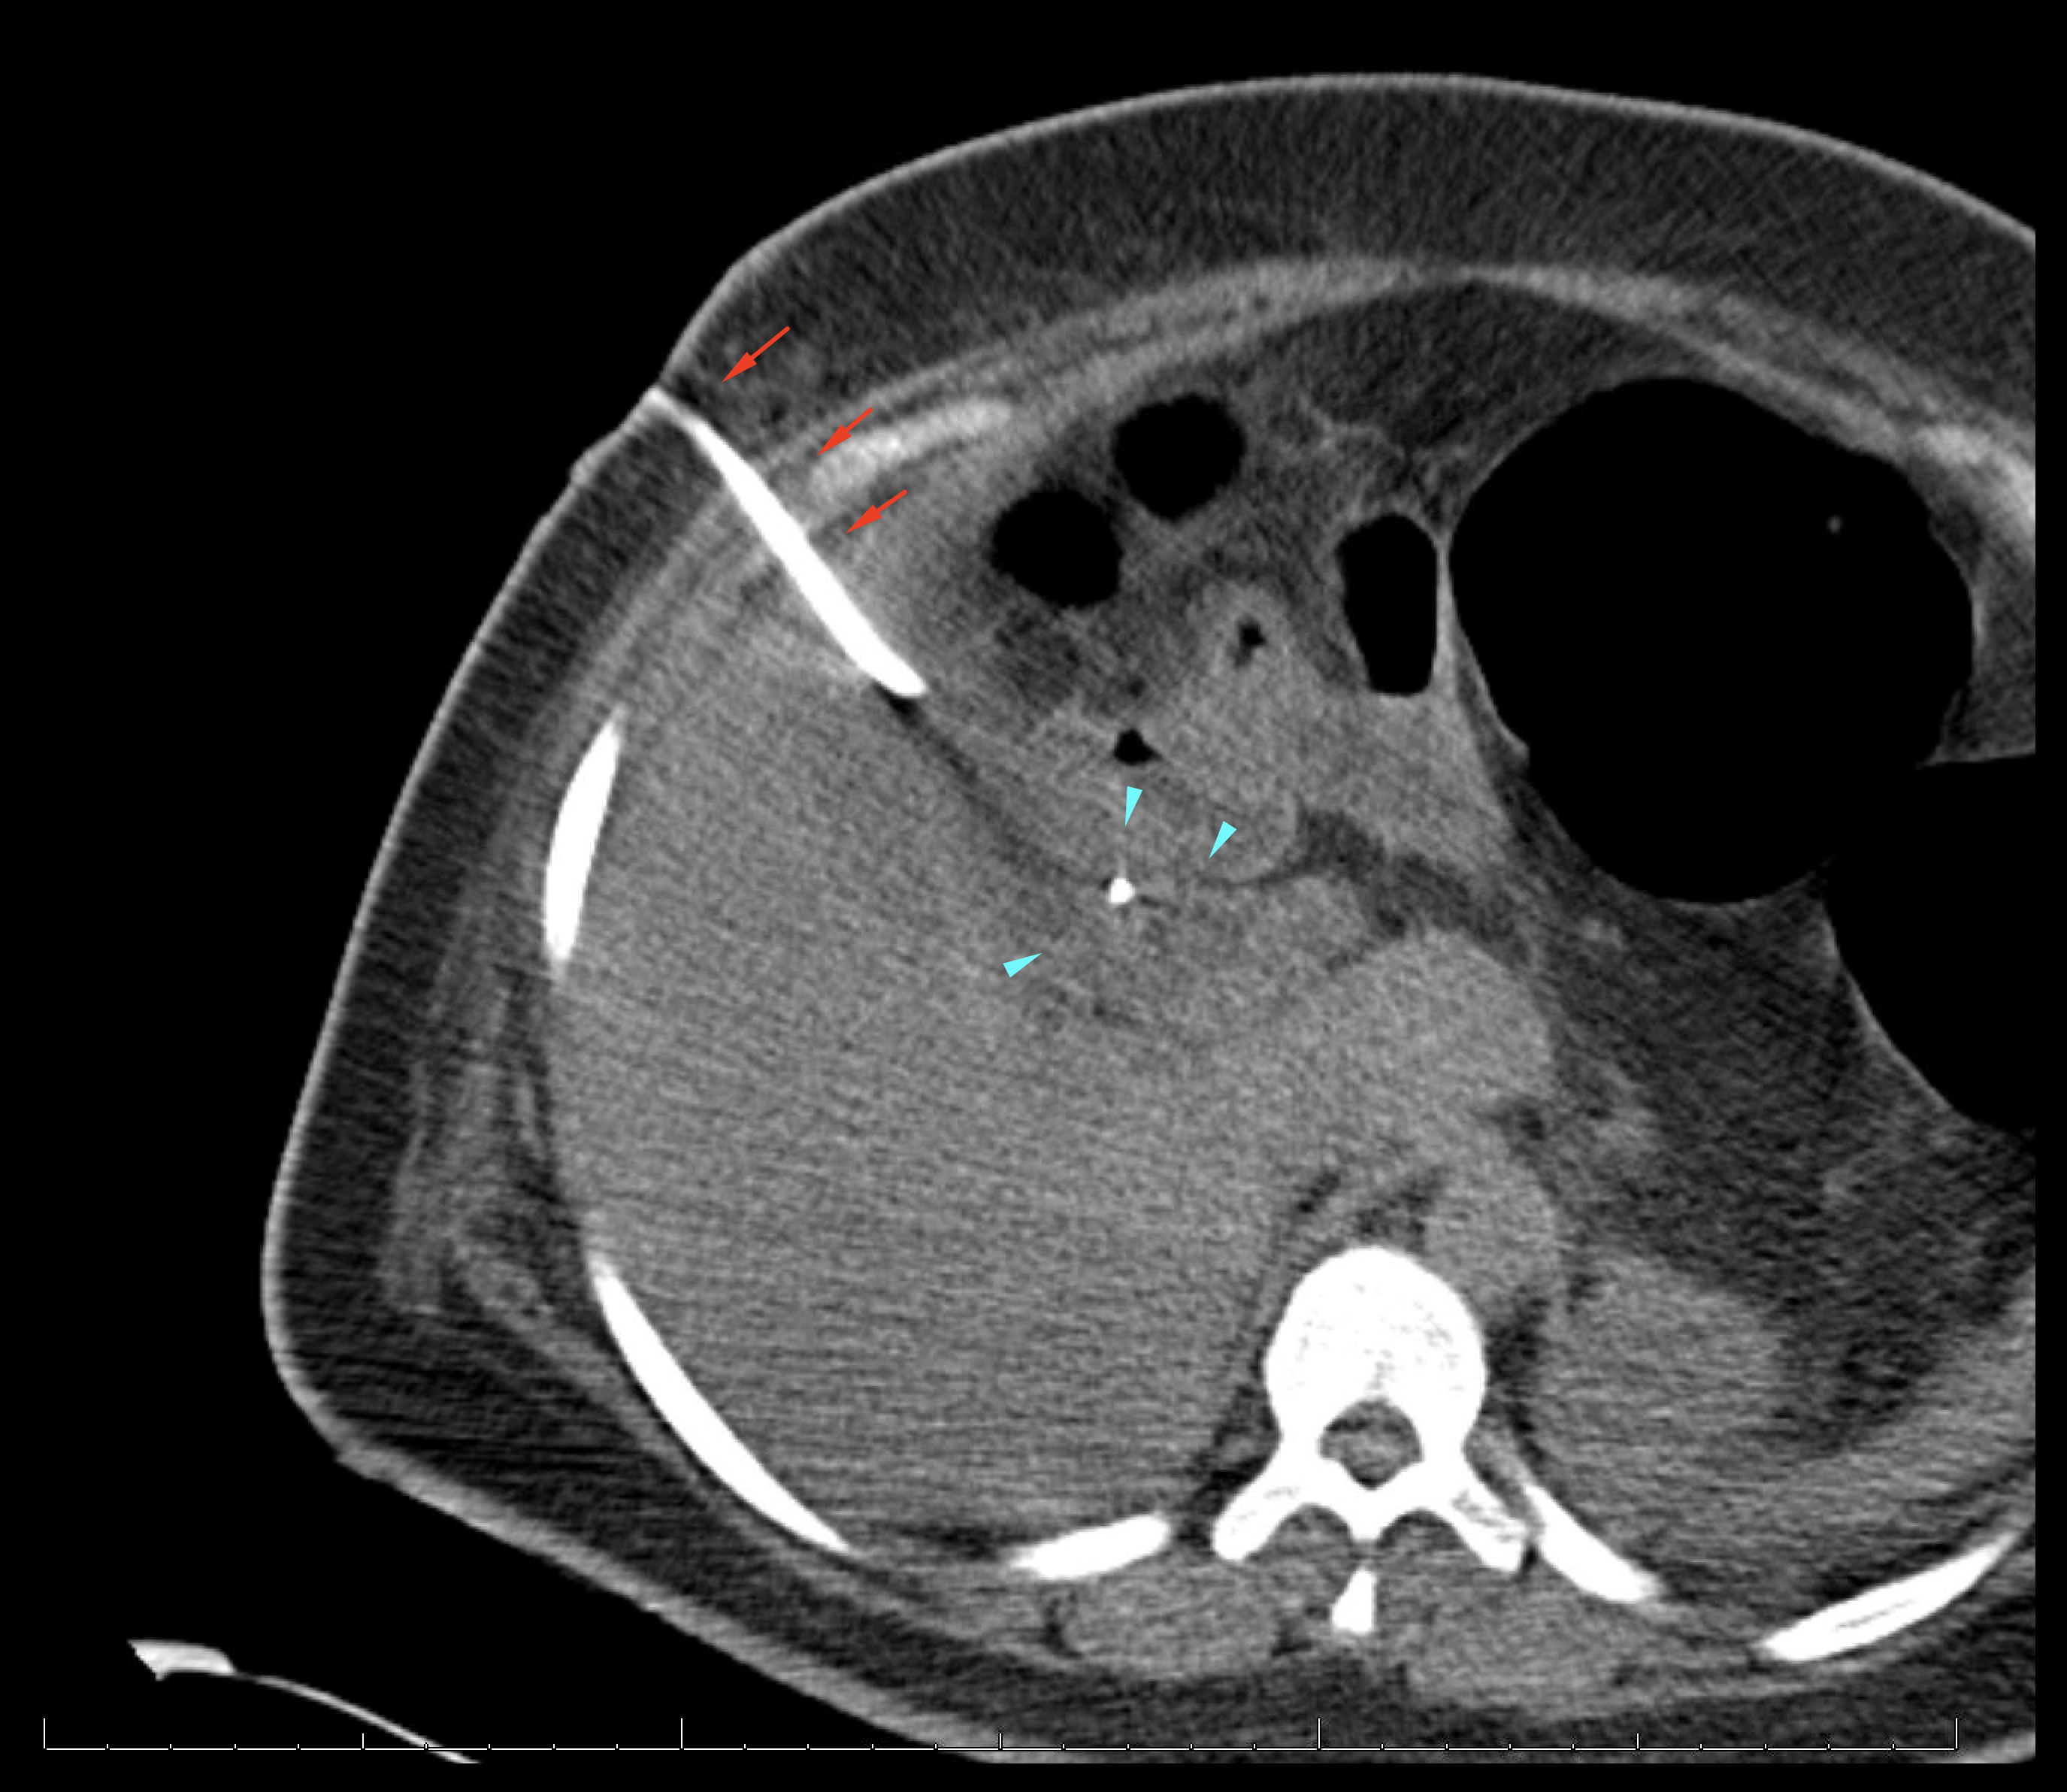

Age: 44

Sex: Female

Indication: Right upper quadrant pain, recent cholecystectomy

Radiotracer: Tc99m Mebrofenin

Sample ReportPostoperative biliary leak drained by the existing surgical drain. Small collection of bile in the gallbladder fossa.

No evidence of biliary duct obstruction.